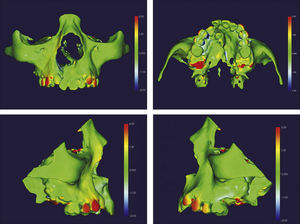

O surgimento e o aumento da acessibilidade da TCFC agregaram uma maior credibilidade ao diagnóstico clínico e às investigações científicas no estudo das deformidades craniofaciais19. Todavia, as informações 3D fornecidas pelas TCFC ainda vêm sendo rotineiramente analisadas de forma 2D, por medidas lineares em cortes ortogonais5,20. A construção e sobreposição de modelos virtuais 3D ainda é uma metodologia pouco difundida. Este estudo é um dos pioneiros que utiliza este método para avaliação de ERM em pacientes com fenda. A sobreposição baseia‐se na construção dos modelos virtuais 3D, utilizando o software SLICER21, pelos arquivos obtidos na TCFC, seguida pela sua justaposição, que utiliza a base do crânio como referência e a final obtenção dos métodos de medidas intitulados: sobreposição por semitransparência e mapa por códigos de cores22. A sobreposição por semitransparência revela uma análise qualitativa, em que o momento pós‐tratamento é retratado por uma malha preta translúcida, sobre o modelo inicial em vermelho (figs. 9 e 10). O aparelho em leque demonstrou um deslocamento de quase todos os dentes para vestibular e uma movimentação vestíbulo‐posterior do segmento menor (lado esquerdo [fig. 9]). O mapa por códigos de cores permite um complemento da análise visual, sendo que cada cor reflete uma alteração na posição das estruturas: azul – recuo; verde – estabilidade e vermelho – expansão. A intensidade da cor está diretamente relacionada à quantidade de movimentação. Todo o mapa é seguido por uma escala, com os valores em milímetros para cada cor (figs. 11 e 12). A observação feita na sobreposição por semitransparência do expansor em leque é confirmada no mapa por código de cores e nas medidas lineares. Uma menor porção de vermelho é visualizada em molares, quando comparada aos pré‐molares. O deslocamento para posterior e vestibular do menor segmento é constatado pela presença de azul na mesial dos dentes e vermelho nas eminências alveolares do lado em questão. Diferentes tonalidades de azul são vistas na cervical dos incisivos, possivelmente uma retroinclinação em decorrência da ausência de apoio mecânico no local. Para a quantificação das mudanças no posicionamento dentário, primeiramente identificou‐se, nos 3 cortes ortogonais, os pontos de referência para a medida (ponta da cúspide mésio vestibular dos primeiros molares superiores e ponta da cúspide dos caninos), tanto do lado direito como do lado esquerdo, utilizando o software ITK Snap23. Os pontos foram marcados com uma esfera de 0,5mm de diâmetro, identificando a posição 3D destas referências no espaço (fig. 13). A aferição das distâncias Euclidianas entre as esferas foi realizada com o auxílio da ferramenta Q3DC no programa SLICER23. O paciente A obteve um aumento de 3mm na distância intercanina e de 6mm na distância intermolar. Na elucidação do paciente que utilizou o disjuntor mini‐Hyrax invertido com BTP (B), observa‐se na sobreposição por semitransparência um deslocamento vestibular, principalmente dos pré‐molares e uma constância das demais áreas, achados corroborados no mapa por código de cores. A área que não está verde é a região de pré‐molares, vermelho por vestibular e azul por palatino, notando uma tonalidade entre verde e vermelho (amarelo) no corpo da maxila do lado menor (esquerdo). A oclusal dos molares, em vermelho, representa a erupção dos elementos.

Sobreposição com semitransparência dos modelos 3D do tratamento com o aparelho em leque. Antes da expansão representado por vermelho e após a expansão pela malha fina translúcida. Observa‐se um trespasse da malha preta para vestibular em molares, pré‐molares e canino, indicando que houve expansão em toda essa região.

Sobreposição com semitransparência dos modelos 3D do tratamento com o aparelho mini‐Hyrax invertido com BTP. Antes da expansão representado por vermelho e após a expansão pela malha fina translúcida. Observa‐se um trespasse da malha preta para vestibular na região dos pré‐molares, indicando expansão concentrada nessa região.

Os 2 casos clínicos aqui apresentados demonstram um efeito isolado da ERM em pacientes portadores de FLPMCU e não podem ser generalizados como comportamento esperado em ERM de pacientes com fenda. Todavia, é nosso objetivo demonstrar que o expansor em leque não correspondeu com sua indicação, apresentando um comportamento diferente do relatado na literatura24. A quantidade de expansão foi inesperadamente maior na região posterior em relação à anterior. Adicionalmente, objetiva‐se difundir na literatura outra opção terapêutica: o mini‐Hyrax invertido com BTP. Este aparelho correspondeu aos achados anteriores, priorizando a expansão anterior e com mínima, ou nenhuma, interferência em posterior. Demais estudos de ensaio clínico devem ser realizados, aperfeiçoando a metodologia e inserindo novas configurações de expansores maxilares, elucidando de forma embasada os efeitos de cada um. O modo de expansão desejada dita o aparelho a ser usado, e essa escolha afeta diretamente o tratamento e prognóstico do paciente.